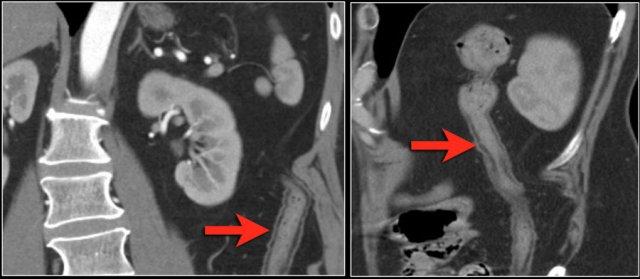

Đôi khi, tái tạo ảnh mặt phẳng coronal dạng lát cắt dày (thick slab coronal reconstructions) có thể hữu ích trong việc đánh giá mức độ ngấm thuốc.

Điều này được minh họa rõ ràng ở bệnh nhân này, trong đó hỗng tràng ngấm thuốc tốt (vùng xanh lá), trong khi hồi tràng giảm ngấm thuốc (vùng đỏ) do thiếu máu cục bộ.

Đây là một trường hợp tắc ruột quai kín khác.

Lưu ý sự khác biệt về mức độ ngấm thuốc giữa các quai ruột bình thường không giãn (mũi tên xanh lá) và các quai ruột giãn bị thắt nghẹt (mũi tên đỏ).

Ở trung tâm là các mạch máu mạc treo bị xoắn vặn (mũi tên vàng).

Các hình ảnh này thuộc về bệnh nhân bị tắc ruột non dạng quai kín.

Lưu ý nhóm các quai ruột non có thành dày ở vùng bụng trên phải (mũi tên vàng).

Phù nề mạc treo ruột (mũi tên đỏ) cho thấy tình trạng tăng áp lực tĩnh mạch do thắt nghẹt.

Giãn mạch máu

Tăng áp lực tĩnh mạch trong thắt nghẹt cũng dẫn đến giãn tĩnh mạch (mũi tên vàng).

Bệnh nhân này cũng có tắc ruột dạng quai kín với kiểu ngấm thuốc xám của các quai ruột bị thắt nghẹt (mũi tên đỏ).

Lưu ý sự ngấm thuốc bình thường của ruột non ở phía trên vị trí tắc nghẽn (mũi tên xanh lá).

Một bệnh nhân khác với hình ảnh ruột thiếu máu cục bộ và phù nề mạc treo ruột lan rộng.

Trong phẫu thuật, toàn bộ đoạn ruột non này đã bị hoại tử.